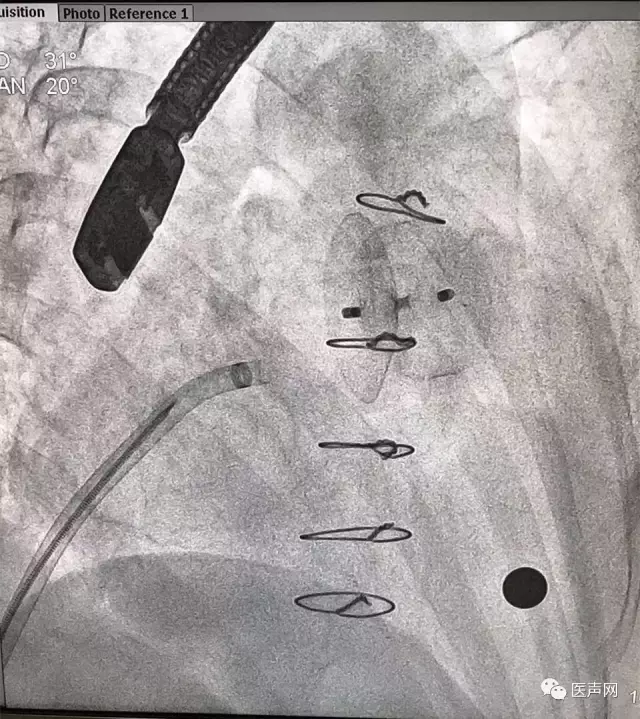

ACP放置

ACP成功释放